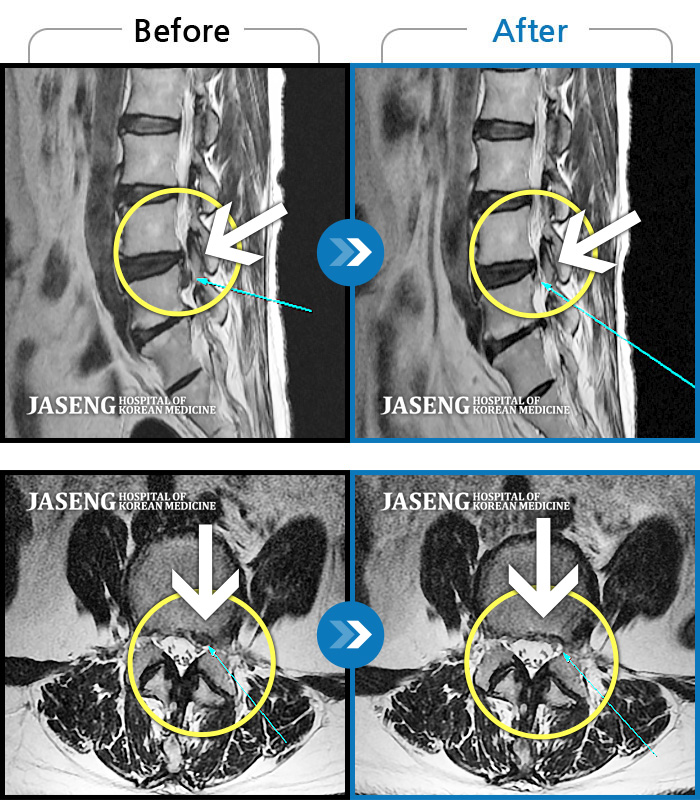

허리디스크

분당 · 진은석 원장

허리 통증 및 좌측 다리 마비 증상

촬영시기

2019.03.25 ~ 2019.11.04

2020.01.10

조회수 3,897